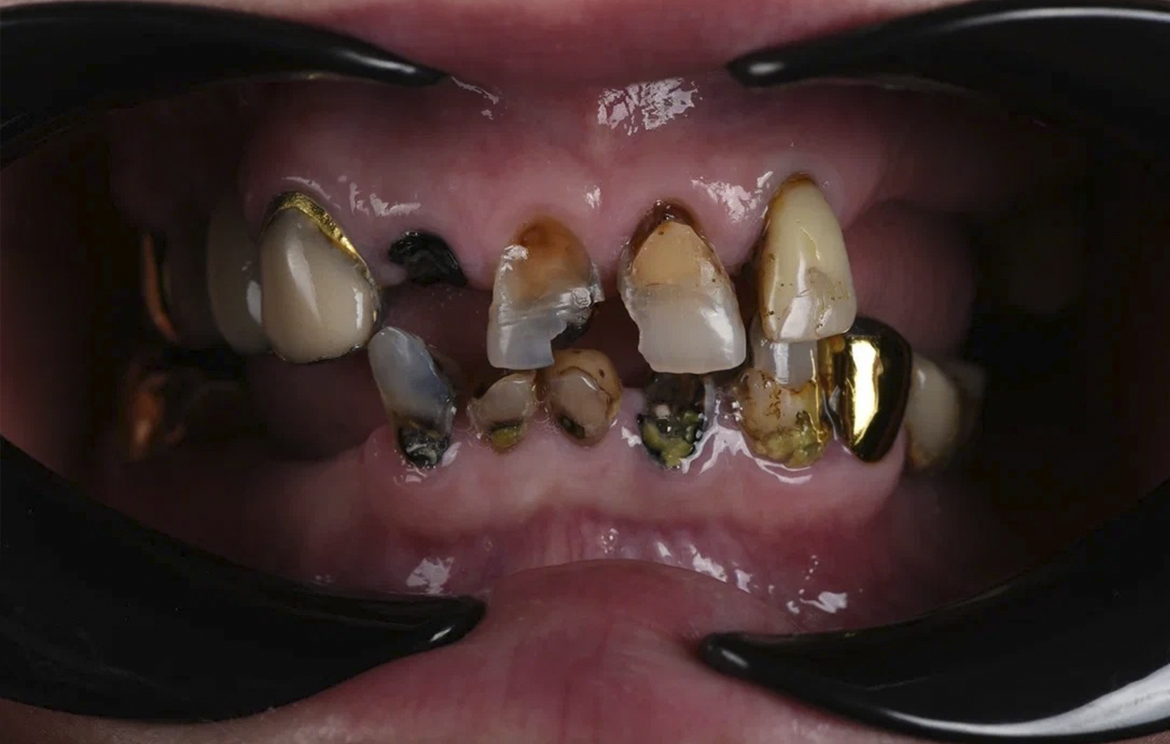

Наши работы